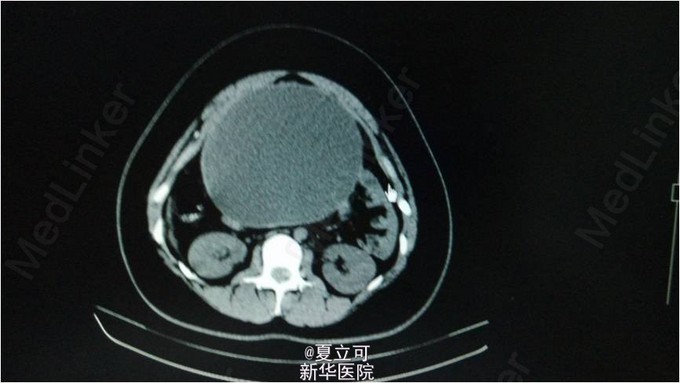

患者,女,21岁。患者1月无明显诱因下出现阵发性左下腹痛,疼痛为刺痛,伴有纳差、恶心感,无呕吐,无发热、腹泻、反酸等。 查体:腹平软,脐周偏左压痛,无反跳痛及肌卫,肝脾肋下未及,移动性浊音阴性,肠鸣音正常。 辅助检查:血常规:CRP 38mg/L,白细胞计数 10.21 10^9/L,肝肾功能、电解质、心肌酶谱、肿瘤指标均未见明显异常。 诊断:左卵巢浆液性囊腺瘤伴出血坏死 治疗过程及结果:入院后1天,患突发全腹疼痛,伴有大汗、心悸不适,当时心率103次/分,血压138/85mmHg。查体:腹紧张,压痛,腹部可及巨大包块,质软。急查腹部CT平扫:腹盆腔巨大囊性占位。阴超:巨大盆腹腔囊性包块,宫底部前方实性包块,腹水。腹部MRI:左下腹及盆腔可见巨大囊性病灶,大小约19*13*23cm。考虑左侧卵巢来源囊腺瘤。后于全麻下行腹腔镜探查+腹腔镜左附件切除+粘连松解术,术中冰冻:左卵巢浆液性囊腺瘤伴出血坏死。术后抗炎补液等对症支持治疗后,症状好转出院。 随访一个月未在出现腹痛症状。 经验:该患者为年轻女性,以反复左下腹痛入院,除消化道疾病外还需考虑妇科疾病,如宫外孕、卵巢囊肿等。该患者虽外院检查提示妇科超声未见明显异常,但最终证实为卵巢囊肿蒂扭转,故提示在临床工作中,不能过分依赖辅助检查,仍应以对病人临床症状观察为主导,结合相关辅助检查协助诊治,必要时复查相关检查十分重要。该病例诊治过程中处置及时,故预后好。